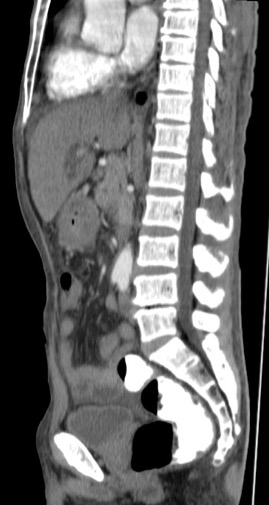

Gastric abnormalities show nonspecific gastrointestinal symptoms and similarly radiological findings. Intra and extra luminal gastric wall thickening are the most common finding in benign and malignant pathologic process. This aim of this case report was to describe several characteristics such as the location and size of the lesion, involvement of the gastric wall and surrounding structures, calcifications, and contrast enhancement pattern which can assist in radiological diagnosis. Several cases at our institution have similar gastrointestinal complaints, however, there were different lesions characteristic found in contrast enhanced abdominal CT scan. The first case 72-years-old man experienced hematemesis with radiologic finding diffuse gastric mucosal thickening as well as homogenous contrast enhancement but without calcification. The second case 37-years-old man complaint dizziness and melena with radiologic finding large tumor more than 10 cm in size, amorph calcification and heterogenous contrast enhancement. The last 60-years-old man case experienced melena and hematemesis, from abdominal CT scan showed irregular gastric mucosal thickening with heterogenous contrast enhancement and fat stranding around the lesion, without calcification. Methods used in these cases were contrast-enhanced abdominal CT scan, esophagogastroduodenoscopy (EGD), and biopsy in order to determine the diagnosis. Contrast-enhanced abdominal CT scan plays a vital role in describing the lesion characteristics which affects the determination of treatment options and future prognosis.